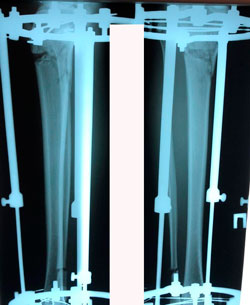

Исходник - 24 года.

Диагноз: врождённое укорочение правой голени на 4 см.

Дата операции - 10.07.2019г.

Костный регенерат в динамике, в процессе удлинения.